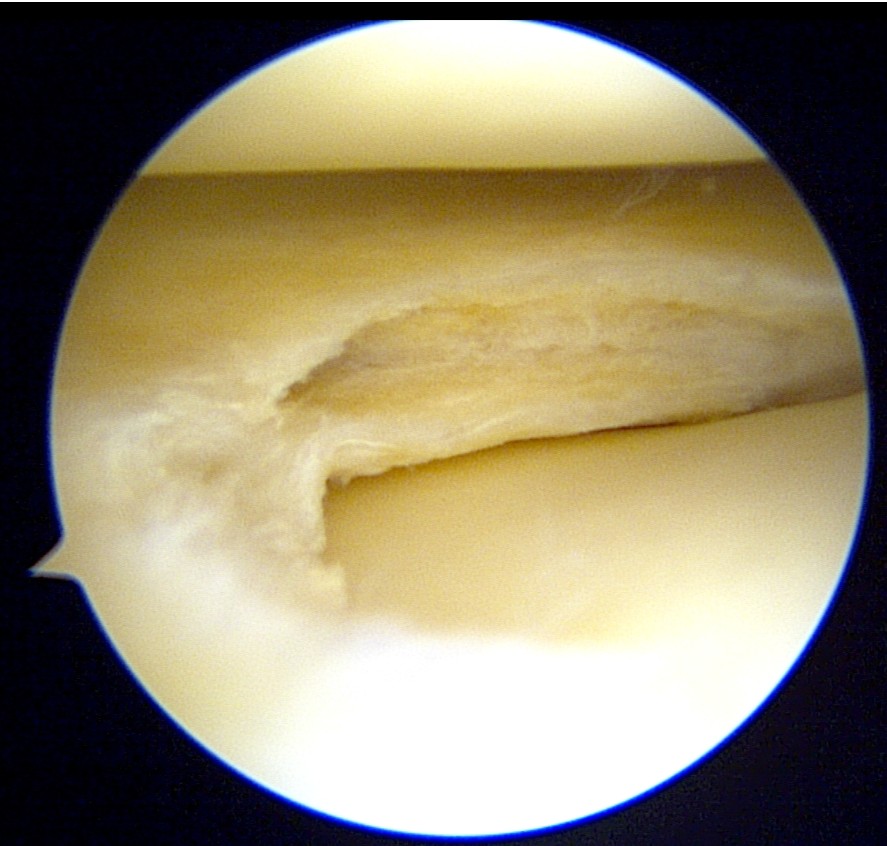

During arthroscopy, a horizontal cleavage tear in the lateral meniscus could be seen.

The cyst material was decompressed as much as possible through the tear.